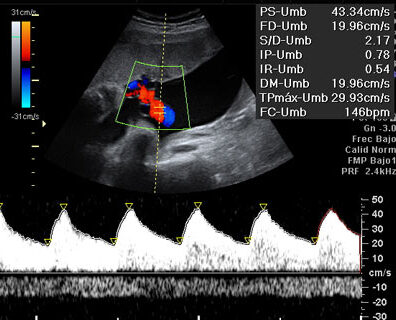

👶🌿 Doppler fetoplacentario

El Doppler fetoplacentario es una ecografía especial que evalúa cómo está circulando la sangre entre el bebé y la placenta, y dentro del bebé.

Es una ecografía que utiliza tecnología Doppler para medir el flujo sanguíneo en los vasos del bebé y la placenta.

1️⃣ Circulación en el cordón umbilical

Evalúa si la placenta está funcionando adecuadamente.